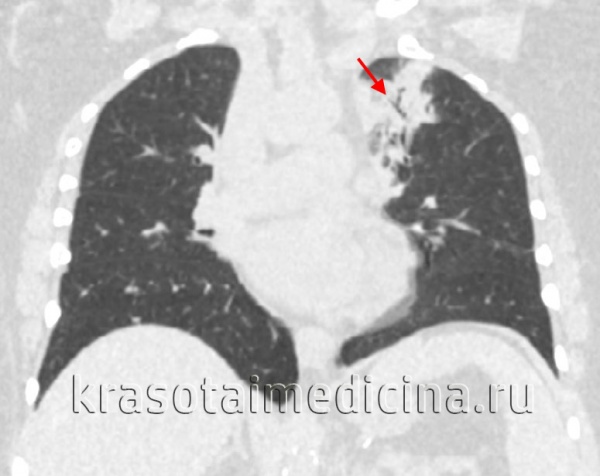

КТ ОГК. Участок пневмонической инфильтрации в верхней доле левого легкого.